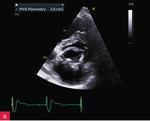

Rycina 9A-C. Kontrolne badanie echokardiograficzne przezklatkowe (TTE) po 5 miesiącach od rozpoznania uwidoczniło porównywalne wymiary zmiany guzowatej jak w badaniu wyjściowym (A), brak progresji zwężenia zastawki mitralnej (B), charakterystyczny obraz uwapnionej otoczki z bezechowym rdzeniem wewnętrznym (C)

Biorąc pod uwagę stabilny obraz kliniczny po zastosowaniu leczenia farmakologicznego i zabezpieczeniu chorej stałą stymulacją serca oraz brak istotnej wady zastawki mitralnej, pacjentkę zakwalifikowano do leczenia zachowawczego i obserwacji z regularną oceną echokardiograficzną (ryc. 9).